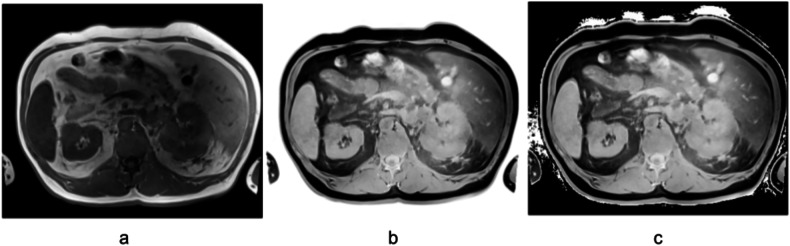

Materials and methods: We retrospectively investigated the performance of two CT-trained models on MRI images: a general multiclass model (TotalSegmentator); and a specialized renal tumor model trained in-house. Both models were applied to 100 T1-weighted (T1w) and 100 T2-weighted fat-saturated (T2wfs) MRI sequences from 100 patients (50 male). Segmentation quality was evaluated on both raw and intensity-inverted sequences using Dice similarity coefficients (DSC), with reference annotations comprising manual kidney tumor annotations and automatically generated segmentations for 24 abdominal structures.

Results: Segmentation quality varied by MRI sequence and anatomical structure. Both models accurately segmented kidneys in T2wfs sequences without preprocessing (TotalSegmentator DSC 0.60), but TotalSegmentator failed to segment blood vessels and muscles. In T1w sequences, intensity inversion significantly improved TotalSegmentator performance, increasing the mean DSC across 24 structures from 0.04 to 0.56 (p < 0.001). Kidney tumor segmentation demonstrated poor performance in T2wfs sequences regardless of preprocessing. In T1w sequences, inversion improved tumor segmentation DSC from 0.04 to 0.42 (p < 0.001).